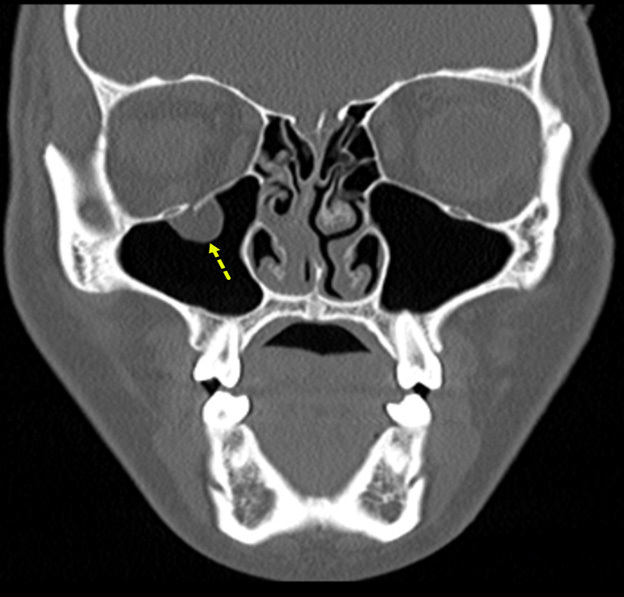

Figure 5 shows an example of an orbital floor fracture without evidence of entrapment in a pediatric patient in the coronal plane. In comparison, Figure 6 shows an entrapped orbital floor fracture in the bone window. The image reveals evidence of a non-displaced orbital fracture with entrapped intra-orbital fat.

Figure 5. Orbital Floor Fracture Without Evidence |

![]() |

The image shows a displaced orbital floor fracture with no evidence of entrapment. Image courtesy of Mantosh S. Rattan, MD, Radiologist, Orlando Health Arnold Palmer Children’s Hospital, Orlando, FL. |

Figure 6. Entrapped Orbital Floor Fracture |

The image shows evidence of a non-displaced orbital fracture with entrapped intra-orbital fat (bone window). Image courtesy of Mantosh S. Rattan, MD, Radiologist, Orlando Health Arnold Palmer Children’s Hospital, Orlando, FL. |